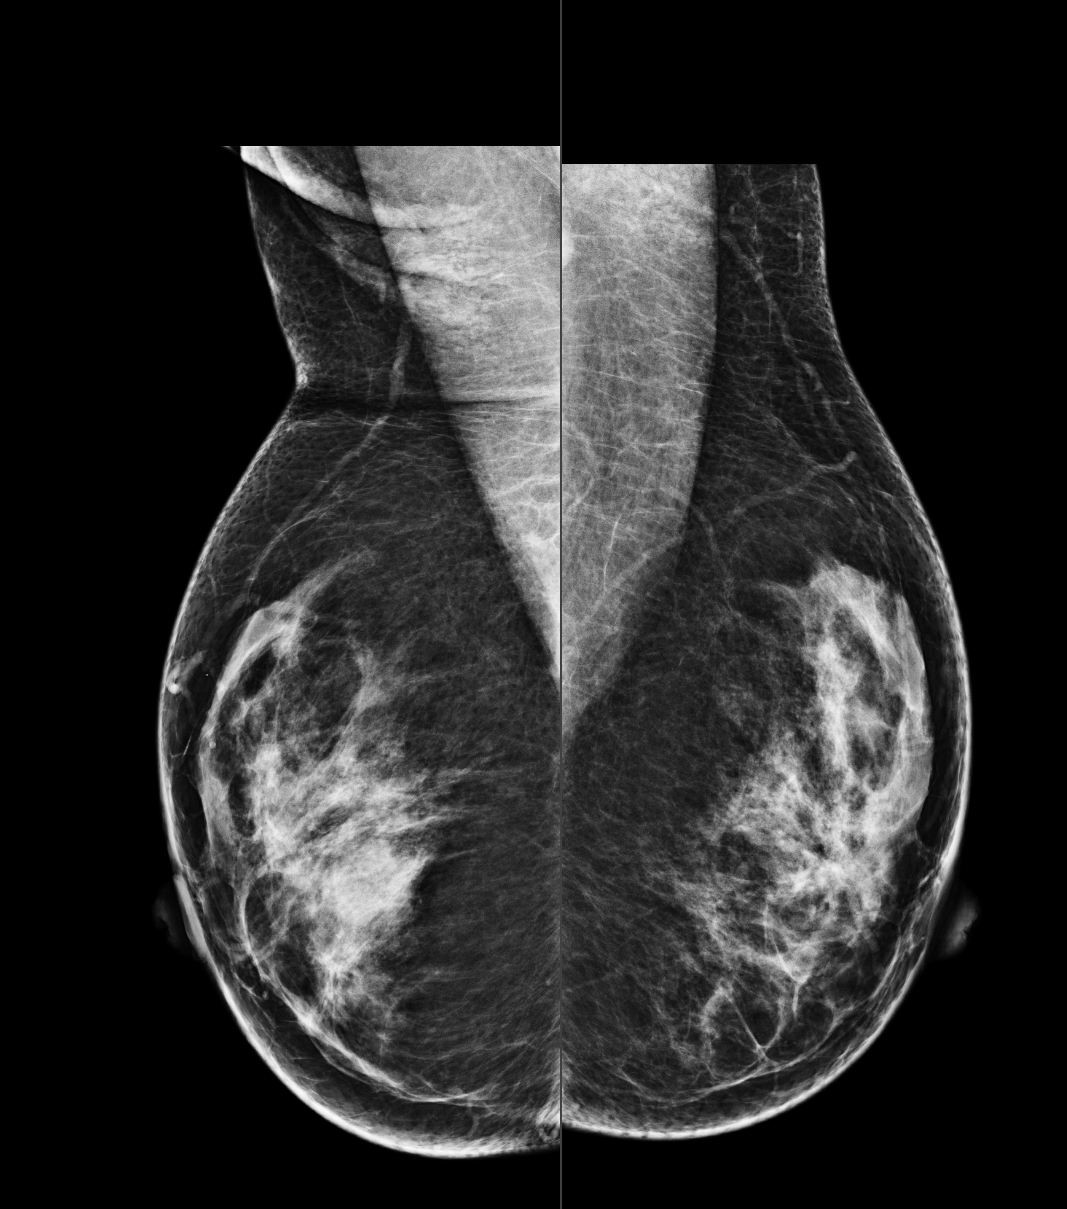

A 45-year-old asymptomatic woman with no family history of breast canc...

Read More